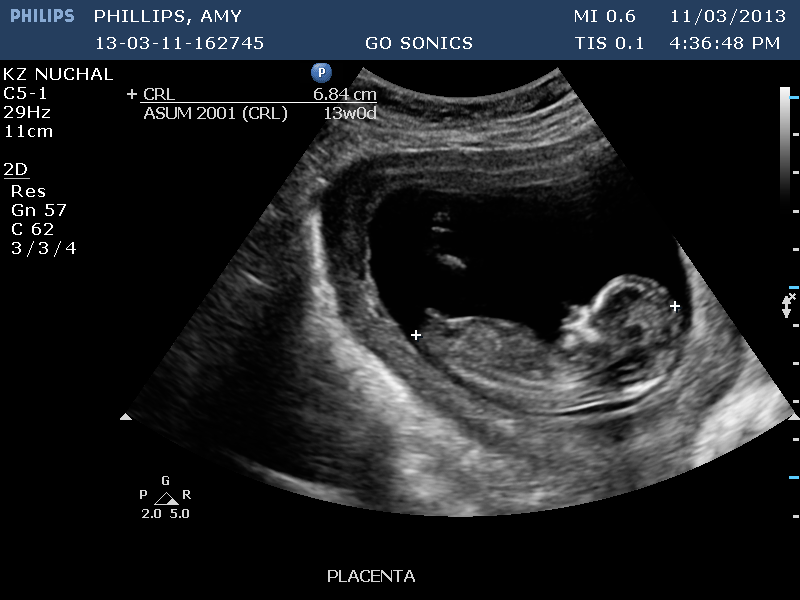

Any guesses greatly appeciated xx

looks quite girly to me! its very parallel to the spine

I honestly think if that was a boy there would be a clear angle at 13 weeks and there is not it looks straight in my opinion

i'm not too sure that is the nub as it looks a little high but if it is - girl